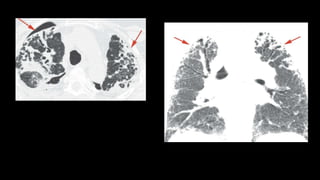

Patterns

• Patchy consolidation or GGO (60%), subpleural and/or peribronchial

distribution

• Small, ill-defined nodules, peribronchial or peribronchiolar

• Large nodules or masses, which may be irregular in shape

• Focal or lobar consolidation

• reversed halo sign or atoll sign m/c drug reactions

• Perilobular pattern m/c with myositis syndromes

• Overlapping features with CEP